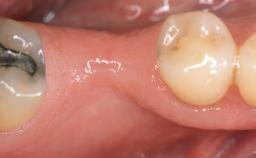

The patient, a healthy 38-year-old woman, was referred for increasing the width of the keratinized tissues at the buccal aspect of dental implant 46. The site exhibited a premature-closure screw exposure caused by trauma during chewing, with inadequate keratinized tissue.